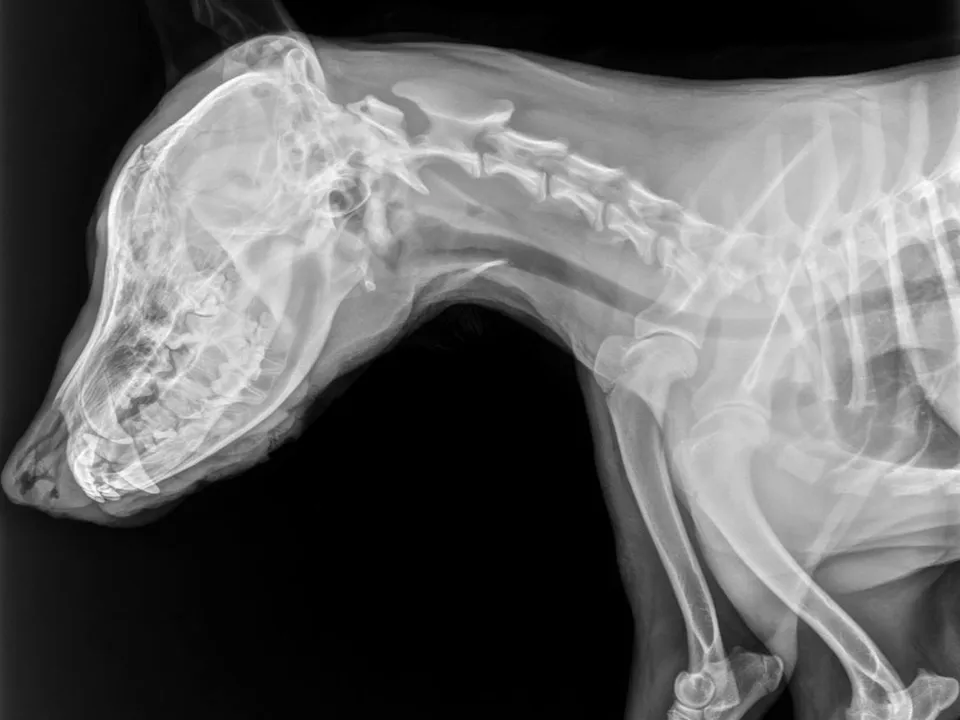

В Подмосковье волонтеры ищут хозяев пса, которому пробили голову на кладбищеИстория потрясла тысячи людей: у Бониса пробита голова, разрезана пасть, множественные раны с опарышами, внутренние повреждения.

Когда пса нашли — на нем был красный ошейник. Очевидно, что он был домашним. Его срочно доставили в клинику, где хирурги во главе с доктором Комаровым провели сложную операцию — некроэктомию, зачистили раны, установили эзофагостому, чтобы четвероногий мог получать питание, несмотря на сильный отек морды.